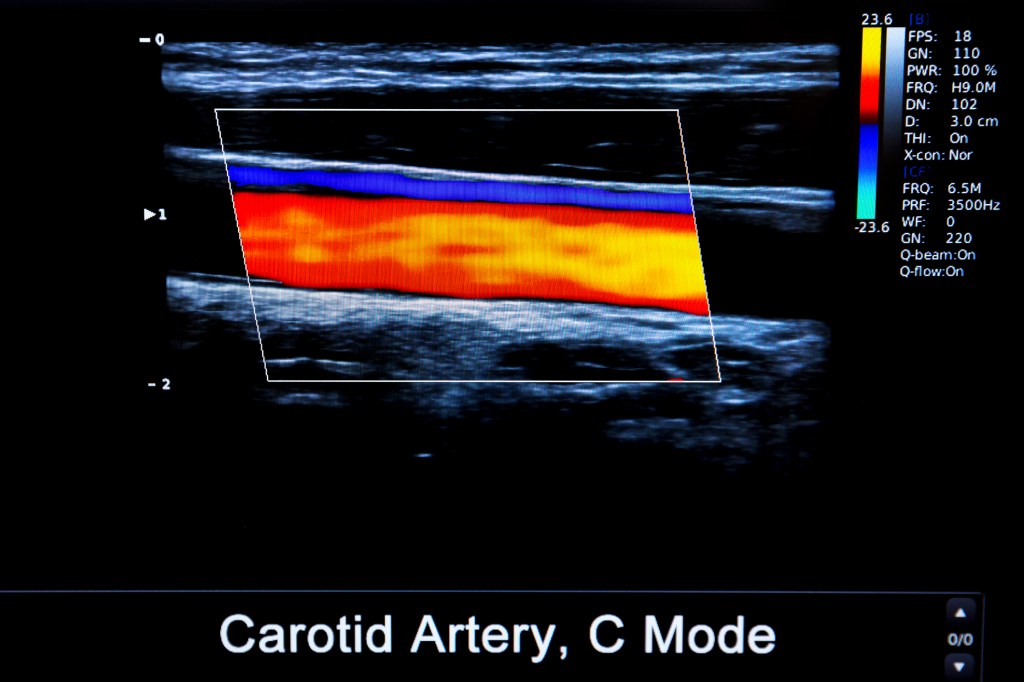

頸動脈超音波利用聲波的反射,由探頭接收之後,由電腦程式判讀,將聲波訊號轉換成影像,不僅可以看到彩色的動態血流,也可以看到血管的順暢程度,以及內皮增厚的狀況。